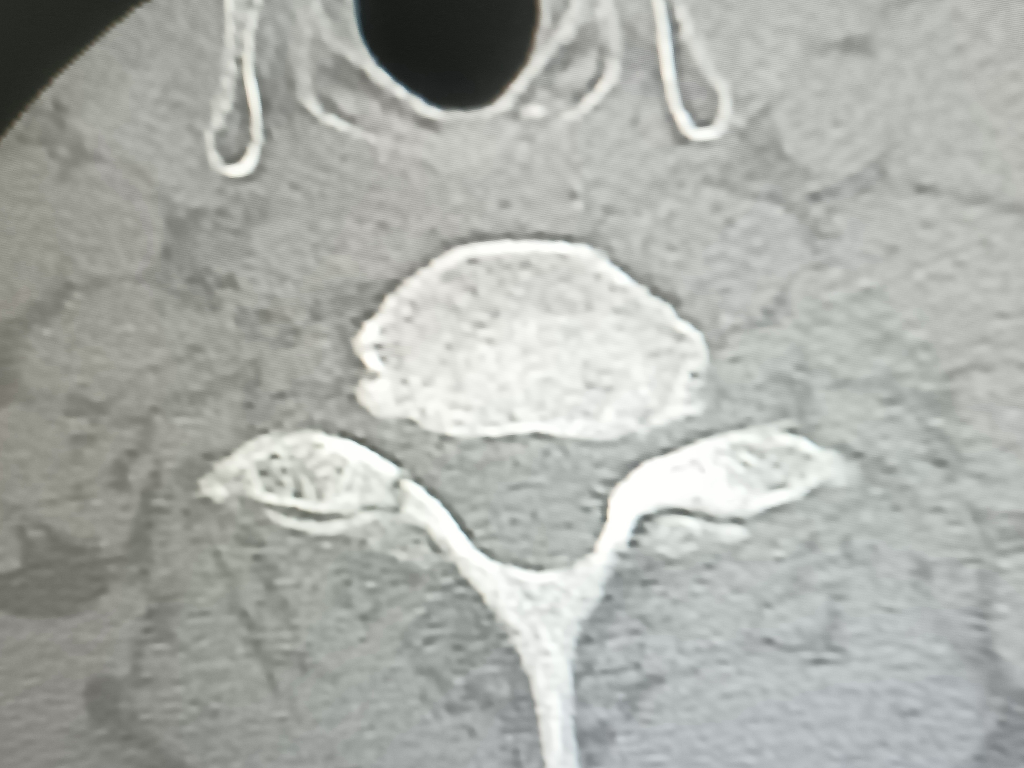

비보호 좌회전에서 파란불에 직진중 상대방차가 과속해서 사고가 났구요 119타고가서 병원에 입원했는데 목보호대만 하고 있는데 4일이 지나도 팔도 안올라가고 상태가 안좋아 mri찍었는데 갑자기 큰병원가서 정밀검사받으라고 그병원 앰블런스로 대학병원 응급실로 왔구요 바로 입원하고 수술하자고.경추6.7번골절 경추5번이 신경을 눌러서 팔이 안올라가는거라고 하네요 다음날 수술하고 잘됐다고 3개월은 지나야 좋아진다고 하는데 수술끝나고 퇴원하라고 하네요 수술한 당사자는 계속 등이랑 팔 가슴쪽 통증을 호소하네요 매일 진통제약이랑 주사 맞고 있는데 약기운 떨어지면 많이 아파해요 ~집가까운정형외과로 가야할거 같은데 아직 정확한 진단주수도 모르고 재활하고 언제쯤 합의해야 하는지 어느 정도 입원해야 하는지 후유장해진단도 받는건지 합의금은 어느정도인지 전혀 모르겠어요 자세한 말씀 부탁드려요

상해정도는 경추골절로 유합술을 시행한 상황으로 충분한 재활 치료를 한후 그에 따른 후유장해진단을 받아야 합니다.